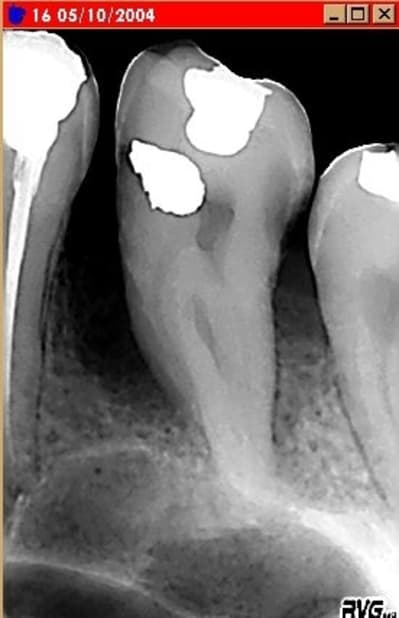

Suite à la demande de Algi, voir le cas suivant:

historique du cas :

Patiente venue en consultation le 19/12/03 .........*douleur et abcé

parodontal sur la 46......poche purulente et grande mobilité verticale

et horizontale.

*presciption d antibiotique + anti inflamatoir........2 detartrages +

equilibration occlusale sur 3 seances........disparition de douleur dès

la 1ere seance.

meulage de la 46 en contact prematurée importante.

A la 3e seance.......disparition des douleurs et de l abcé..............

/voir radio qui montre une destruction importante du septum intra

radiculaire et du septum mesial + une resorption tres importante de la

racine mesiale.